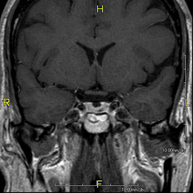

- Neuroradiology

- Brain MRI (cranial)

This non-invasive diagnostic procedure uses an electromagnetic field and radio waves (from a transmitter and receiver) to acquire high-definition anatomical images of the brain. It is a radiation-free procedure. Indicated for: vascular problems, memory loss, epilepsy, headache, malformations, suspected tumour, meningitis.